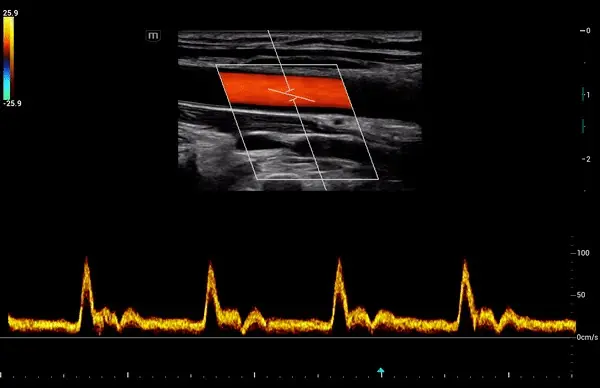

- Doppler espectral: proporciona un análisis gráfico en forma de espectro de las velocidades del flujo, ayudando a diferenciar patrones normales de anormales.

- Doppler pulsado (PW Doppler): permite medir la velocidad del flujo en un punto específico del corazón o un vaso, siendo útil para analizar válvulas cardíacas o flujos intracavitarios con alta resolución espacial. Sin embargo, está limitado por la velocidad del flujo: cuando es muy alta, puede presentarse aliasing (artefactos).

- Doppler continuo (CW Doppler): emite y recibe señales simultáneamente, lo que le permite registrar velocidades de flujo muy elevadas sin aliasing.

- Doppler color: representa el flujo sanguíneo en tiempo real mediante un mapeo codificado por colores, facilitando la identificación visual de turbulencias, flujos retrógrados o alteraciones hemodinámicas. Es clave en estudios de válvulas y comunicación interventricular.